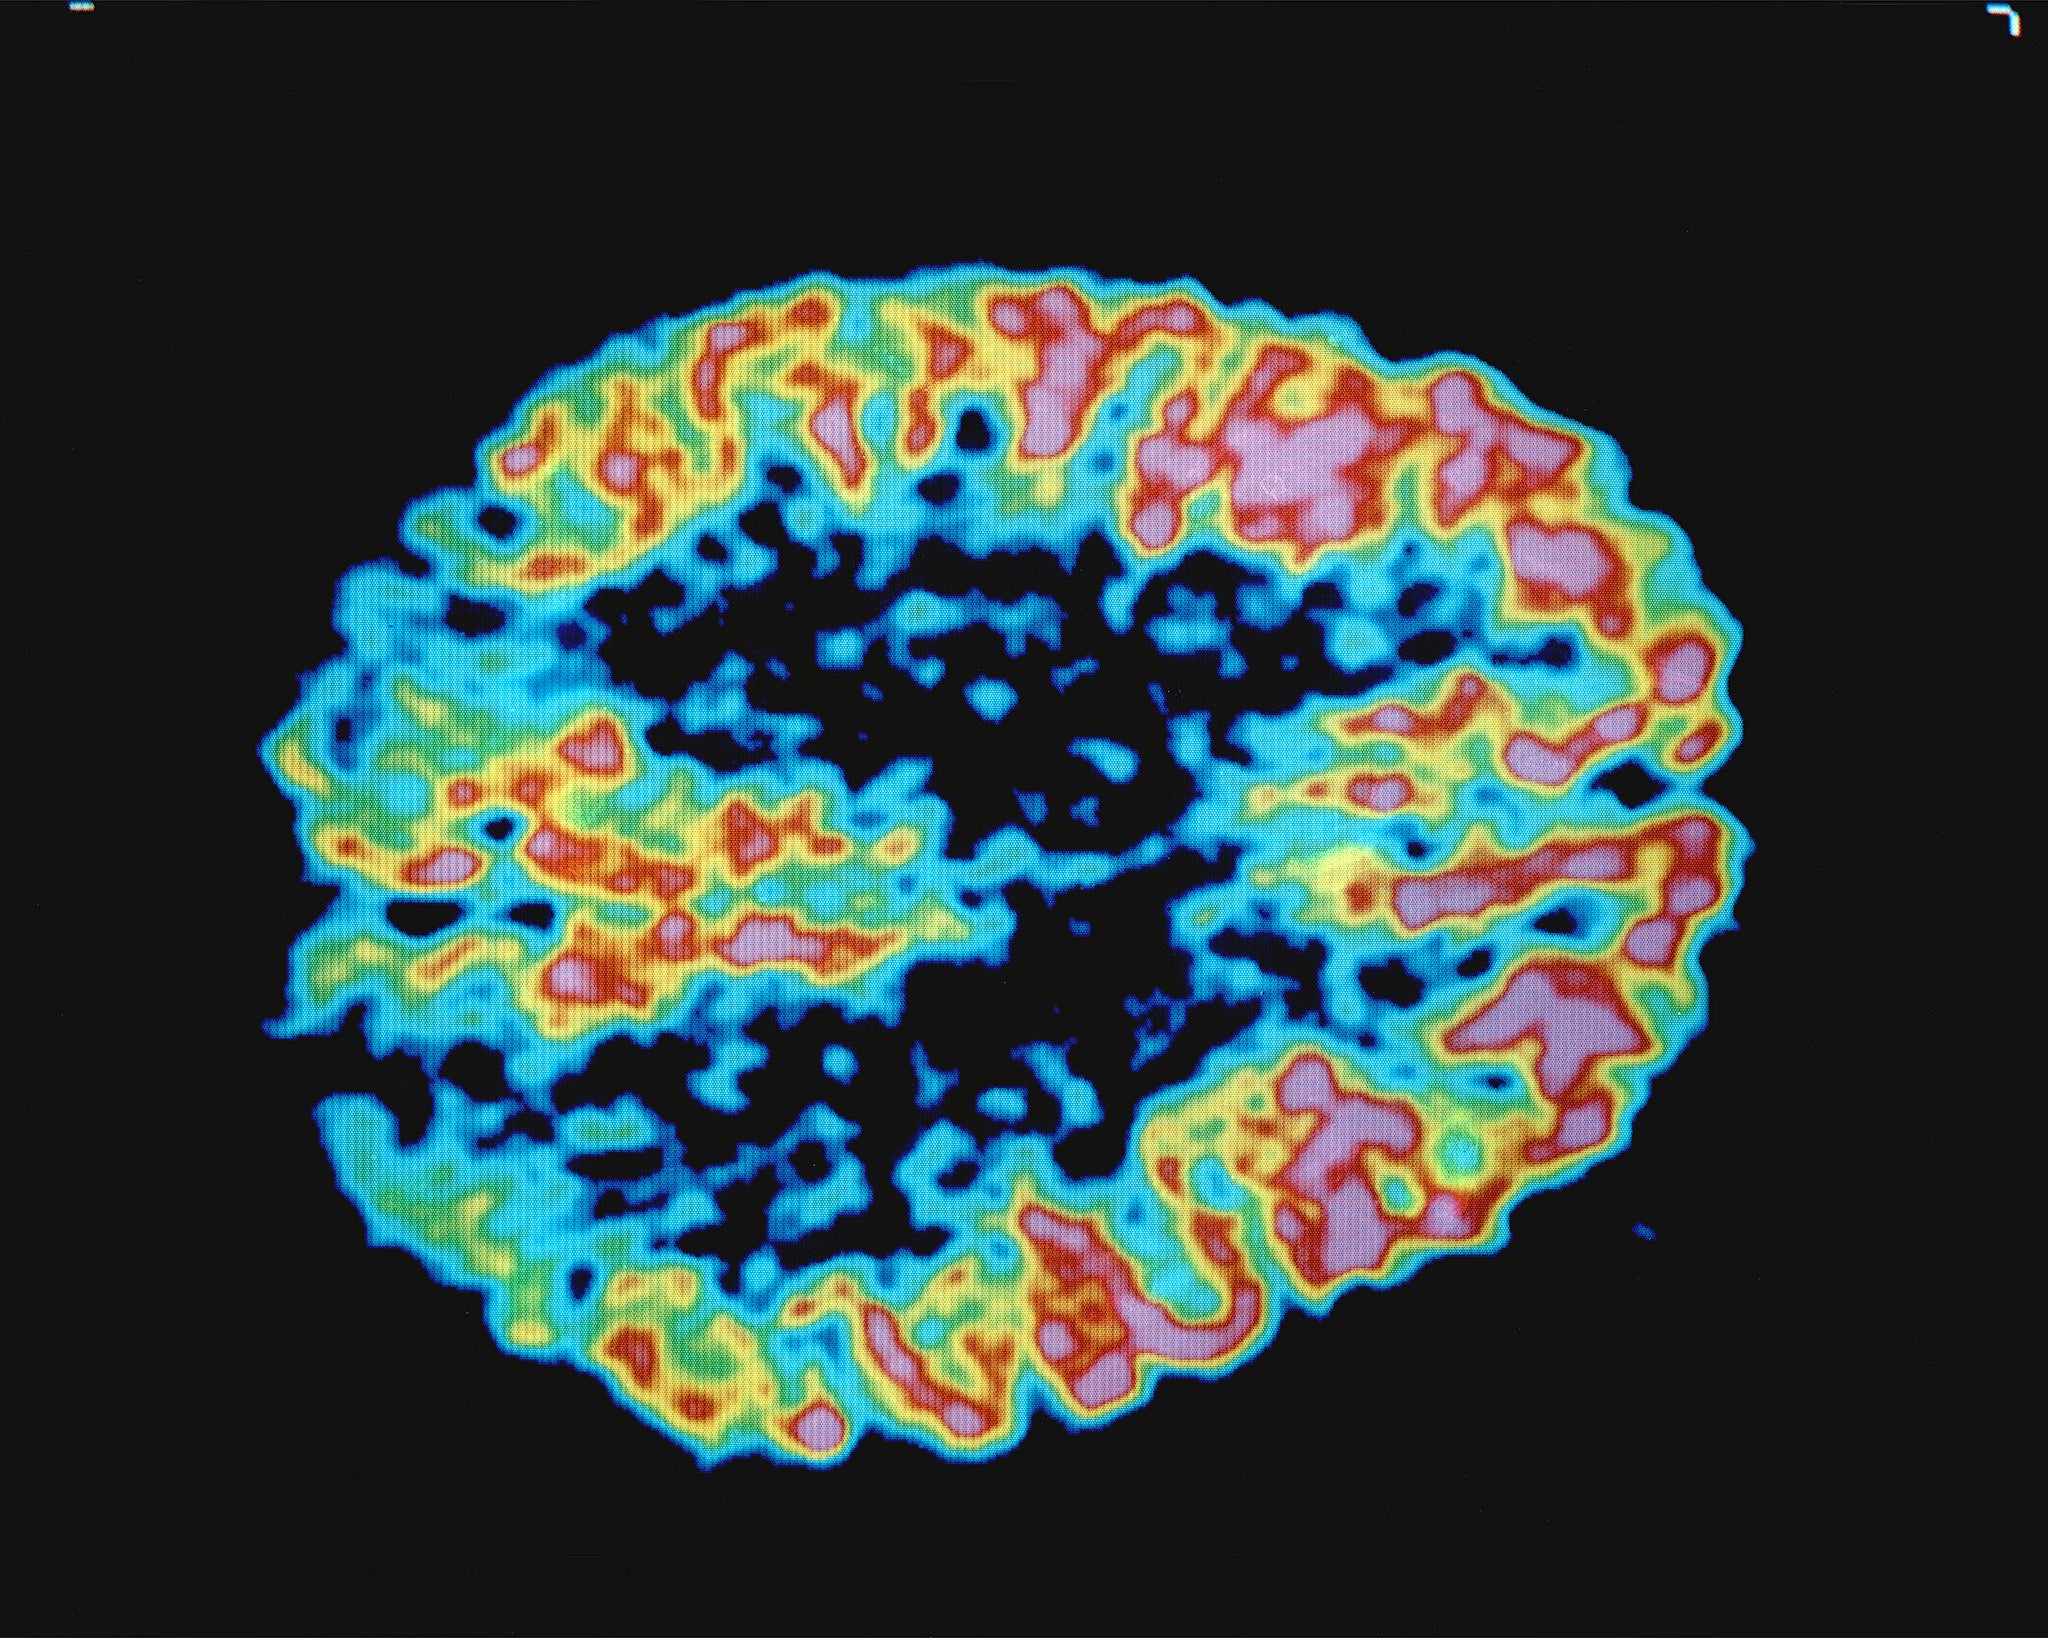

We talk to the director of the Wisconsin-Alzheimer’s Disease Research Center about the research they are doing. We also look at how caregivers can best help Alzheimer’s patients.